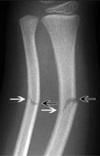

Fratura em galho verde + deformidade plástica

65

Fratura completa